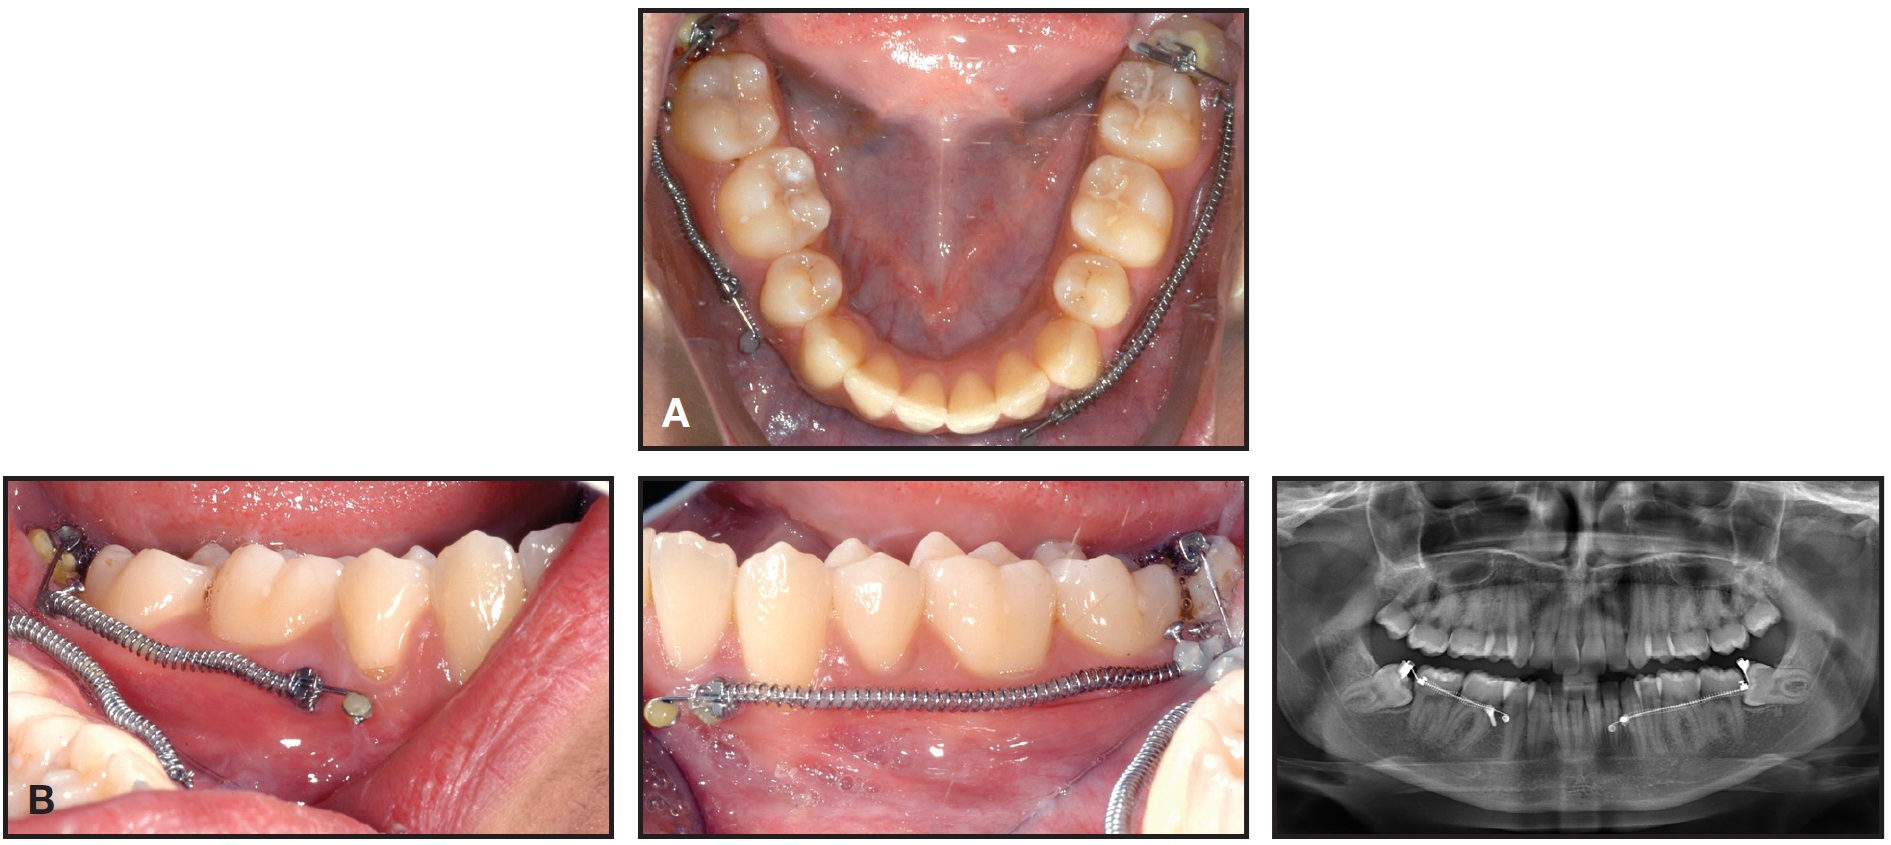

Fig. 4 Case 1. A. Activation of uprighting mechanics. B. One month later.

Six months later, with the third molar fully upright, the appliance was removed (Fig. 5). The lower right third molar was in stable occlusion with its antagonist, but the upper third molars had not yet erupted. Contrary to expectations, the lower left third molar remained in its original vertical position and may require active alignment.

Fig. 5 Case 1. After six months of uprighting, showing stable contact between third molar and antagonist.